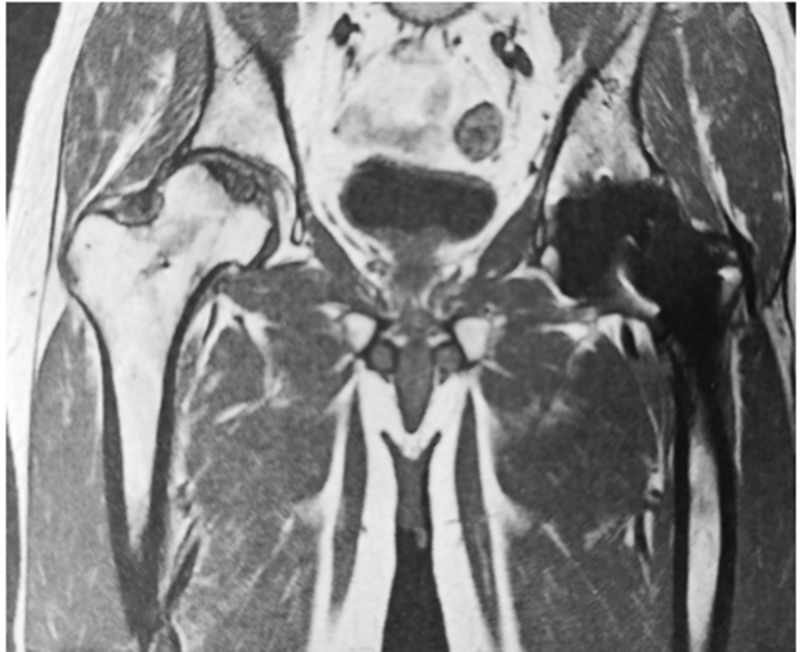

图4 同一患者术后3年,核磁显示右股骨头坏死软骨分离。患者尚未回归工作,坐姿活动无疼痛;跑步或某天剧烈运动后感受到右腹股沟中度疼痛。他对置换一侧的结果很满意,想急于做右侧手术,以便早日恢复职业工作。